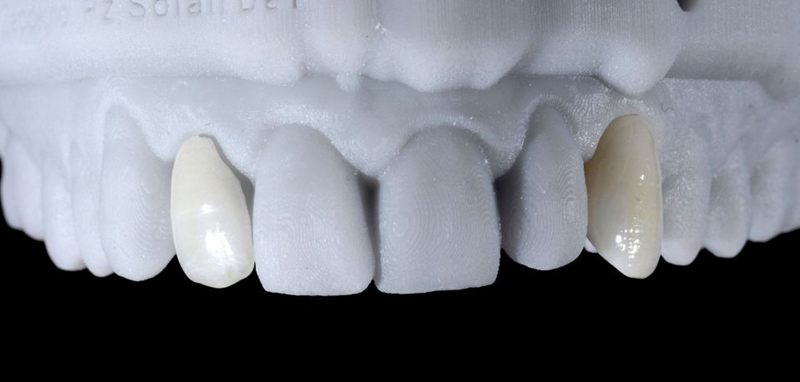

5. 牙科实验室基于数字蜡型(在树脂打印模型上)制作临时牙冠(图 22-24)。

Fig. 22: Lateral view of the printed model: Note that the shape of the provisional canine crown is now in line with the adjacent teeth.

Fig. 23: Provisional crown.

Fig. 24: The occlusal view shows the provisional abutment and...